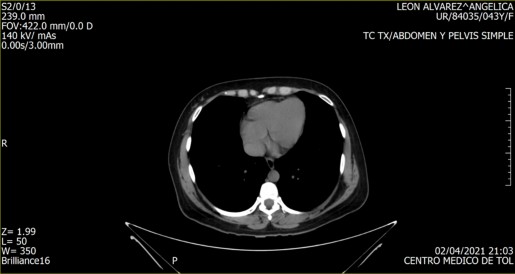

Imagen 1. TC TX. Abdomen y pelvis simple. Captura de video. (Autora, 2021).

Imagen 2. TC TX. Abdomen y pelvis simple. Captura de video. (Autora, 2021).

Imagen 3. TC TX. Abdomen y pelvis simple. Captura de video. (Autora, 2021)

Por supuesto, la producción artística no está exenta de un orden simbólico, mismo que determinará la relación de identificación imaginaria con la obra. Es a partir de esta lógica que se retomó una tomografía de tórax realizada ante un dolor inexplicable en el abdomen, inexplicable, porque le sucedieron diversos estudios que devolvían la interrogante sobre el origen del dolor en cuestión.

La tomografía señaló, entre otras cosas, la existencia de una “morfología ovoidea de bordes tenues y mal definidos, de densidad heterogénea, ya que presenta porciones sólidas y líquidas, mide en su conjunto 116x75mm en sus ejes mayores”. Cabe mencionar que, al revisar una y otra vez los videos que conforman el estudio, es imposible determinar dónde se encuentra la morfología ovoidea. Hay elementos que permiten una relación identificatoria, una pelvis, algún órgano, pero nada que pueda dar cuenta de la morfología en cuestión; fue necesario recurrir al orden simbólico de la medicina alópata para darle un nombre al elemento anómalo.

Adicionalmente, desde el ámbito imaginario se le nombró ‘Benedicto’, haciendo alusión a su carácter significante asociado a lo benigno, pero también al nombre del penúltimo papa, cuya imagen es asociada a un personaje nada benigno e incluso malvado. Bajo este nombre, fue posible establecer una identificación imaginaria con algo ominoso producido por el propio cuerpo y que, a partir de la tomografía, tenía una ambivalencia propia de Schrödinger: era al mismo tiempo benigno y maligno, y solo una intervención quirúrgica podría determinar su estado final.